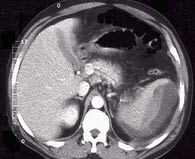

话说,晚上夜班收了个外伤小哥,说是骑摩托车车祸导致闭合性腹外伤。入院后给他做了CT证实:闭合性腹外伤,脾脏包膜下血肿。腹腔少量积液。因病人血压平稳,查血常规也接近正常,且小哥体质较好,决定保守治疗。如果保守治疗有效,避免小哥挨一刀,且可以保住脾脏,向其交代病情,家属也同意,小哥也同意保守。再三向小哥交代,绝对卧床休息,不要活动,观察半月。

脾破裂CT